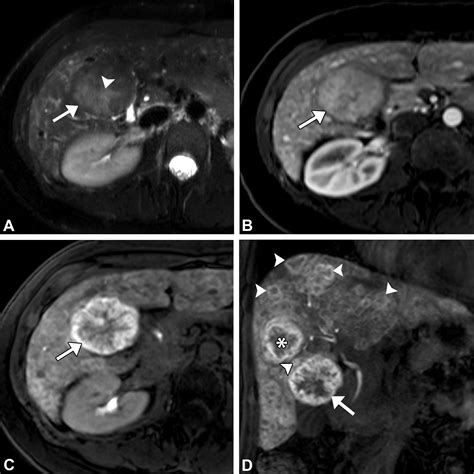

The hallmark of Focal Nodular Hyperplasia is the presence of a central fibrous scar. When radiologists view this mass through imaging technology, this central scar is a key diagnostic feature that helps distinguish it from other types of liver growths, such as hepatocellular adenomas or malignant carcinomas.

• MRI (Magnetic Resonance Imaging): This is the gold standard for diagnosing Focal Nodular Hyperplasia. Using specific contrast agents (like gadoxetate disodium), doctors can observe the unique way the mass absorbs and excretes the contrast, which is highly characteristic of FNH.